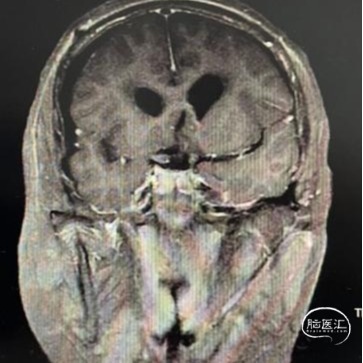

头部MRI显示:鞍区-鞍上区-第三脑室可见一不规则囊状长T1极长T2信号灶,大小约43mm*32mm*43mm,增强后可见病灶不均匀明显强化。垂体及视交叉未见显示,双侧脑室扩张,双侧脑室旁可见对称性斑片状长T1长T2信号灶。

术后MRI